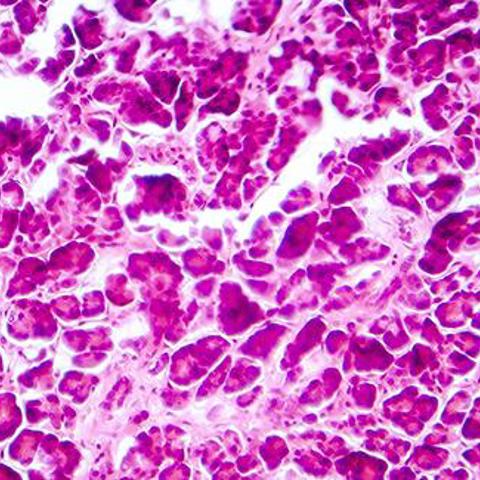

Endothelial cells can be found on the inside of blood vessels. Vessels in the pancreatic islets form a dense network with many small pores in the endothelial cell membrane, facilitating the exchange of molecules across the vessel wall.

Researchers investigated how pancreatic islet vessel formation and function were affected by primary cilia, small hair-like structures found on beta cells and endothelial cells.

For the latest study, researchers examined Bardet-Biedl Syndrome, a disease caused by cilia dysfunction and were able to show that when endothelial cilia are dysfunctional, the blood supply to the pancreatic islets is less efficient. Newly formed vessels have larger diameters and fewer pores that allow nutrients to pass through the vessel wall.